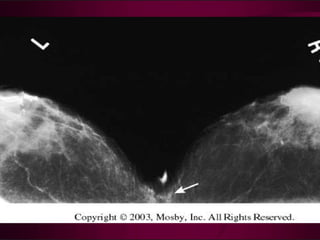

Filling defects d/t intraductal

Carcinoma

Filling defects d/tintraductal Carcinoma